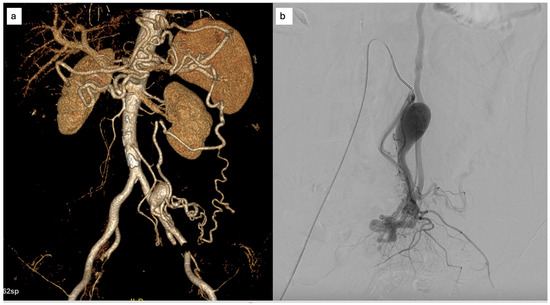

Background/Objectives: Endoscopic biliary stenting is the standard palliative intervention for malignant biliary obstruction, aimed at restoring ductal patency. Radiofrequency ablation (RFA) has been introduced as an adjunct technique to improve stent durability and patient outcomes. However, the literature remains inconclusive regarding which patients are most likely to benefit from the combination of RFA and stenting. Methods: We retrospectively described clinical outcomes of 24 patients undergoing endobiliary RFA combined with biliary stenting for malignant biliary obstruction. Post-procedural and 6-month outcomes were assessed using technical success and changes in serum bilirubin; procedure-related adverse events were extracted from available medical records. Results: Nineteen females and five males were included in the study. The most prevalent diagnoses were metastatic adenocarcinoma (n = 8) and cholangiocarcinoma (n = 6). 25% of patients did not complete the 6-month follow-up due to malignancy progression. 16 out of 18 maintained the patency of biliary stents. Repeat endoscopic intervention for suspected stent dysfunction was documented in one patient. When analyzed in an intention-to-treat manner (counting deaths before 6 months as failures), the corresponding 6-month patency/clinical success rate was 16/24 (66.7%). Conclusions: In this retrospective single-center experience, RFA combined with biliary stenting was feasible and was associated with maintained biliary drainage in a majority of patients who survived to the 6-month assessment.